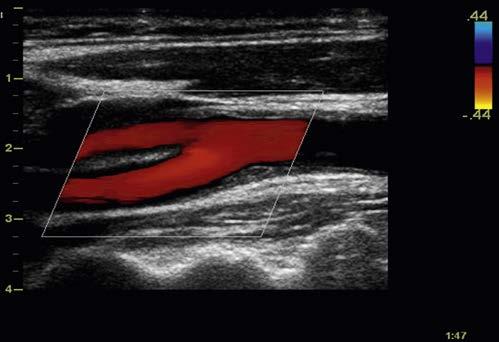

enable color-coded 2D and 3D presentations of Doppler information (color-Doppler displays) to be superimposed on gray-scale anatomic images (Figure 1-13). Doppler information is applied to loudspeakers for audible evaluation and to spectral-Doppler displays for quantitative analysis (Figure 1-14). The spectral-Doppler operation includes

anatomic imaging to determine the location(s) from which the spectral information is acquired (Figure 1-15).

FIGURE 1-14 Spectral-Doppler display of arterial blood flow with presentation of calculated flow velocity data.

FIGURE 1-15 Spectral-Doppler display of blood flow in the carotid artery. The anatomic image shows the location (arrow) from which the spectral-Doppler information was acquired.